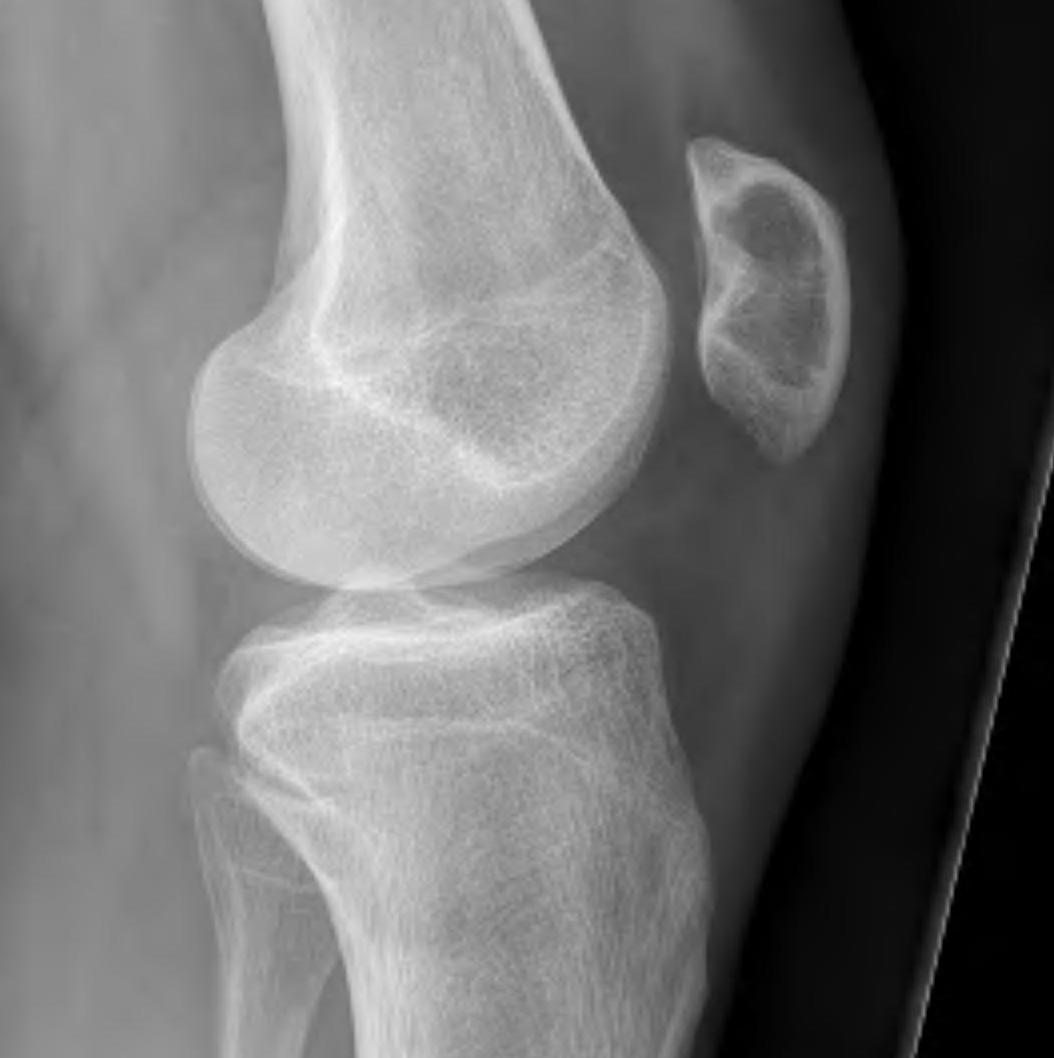

Popliteal fossa / parosteal OS

- posterior approach

- go through hamstrings or gastrocnemius

- depending on whether lesion medial or lateral